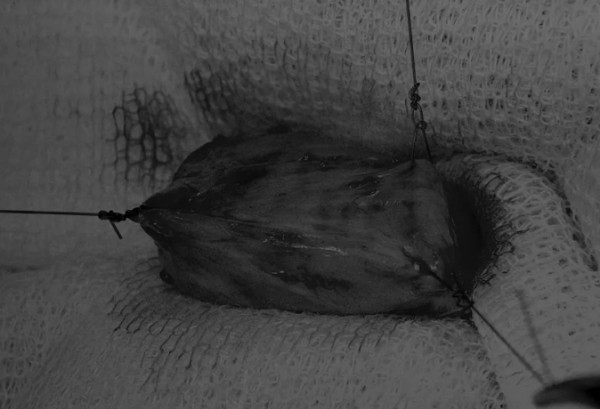

在牵引缝线之间选择血管扩张较差的区域用手术刀切开膀胱壁(图3)。在牵引缝合线之间用手术刀在血管不良的区域做切口。切开膀胱壁后,膀胱内的手术可按手术方案实施,例如取出结石(图4)。

图3 避开主要的膀胱血管,做一个尽可能小的切口

切口可以在膀胱背侧或腹侧进行,避免对大血管的损伤。